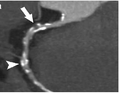

Craniale Computertomographie Abgebildet sind Felsenbein und Nasennebenhöhlen. Aufgrund der hohen Auflösung der Aufnahme des verwendeten 64-Zeilen-CTs sind selbst die Gehörknöchelchen erkennbar. -